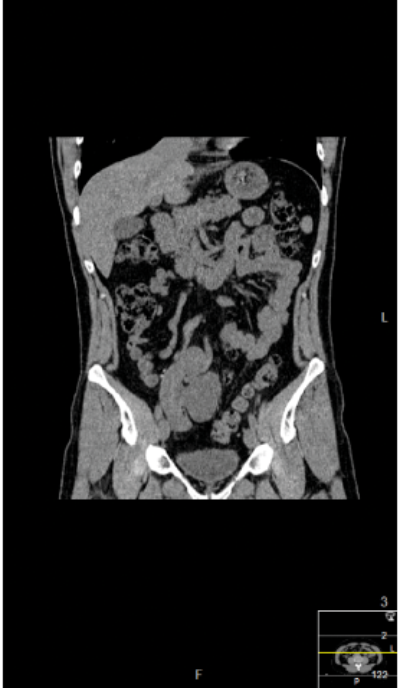

A 44-year-old woman presented with several months of malaise and right flank pain. A CT scan demonstrated a 26 x 25mm upper pole calyceal stone with an adjacent abscess that had perforated the capsule and some adjacent atelectasis. She was transferred from a referring hospital and treated with antibiotics and re-imaged.

CT scan.

Figures above demonstrate worsening hydronephrosis preoperatively.